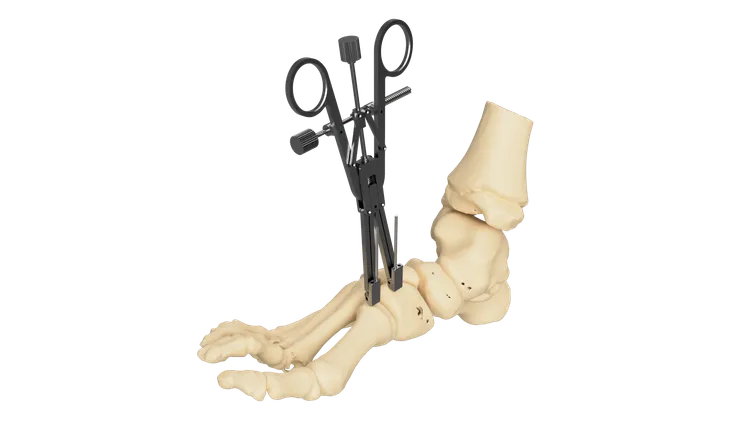

01 Surgical Retractor